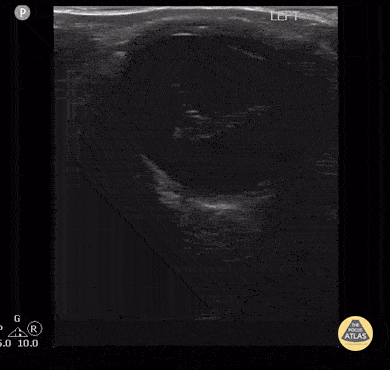

Peds-Orbital - Proliferative Vitreoretinopathy 1 of 2

19 year old with proliferative vitreoretinopathy (PVR) from a suspected chronic/older retinal detachment which had gone undiagnosed for a prolonged period of time. Contributor: Antonio Riera, MD